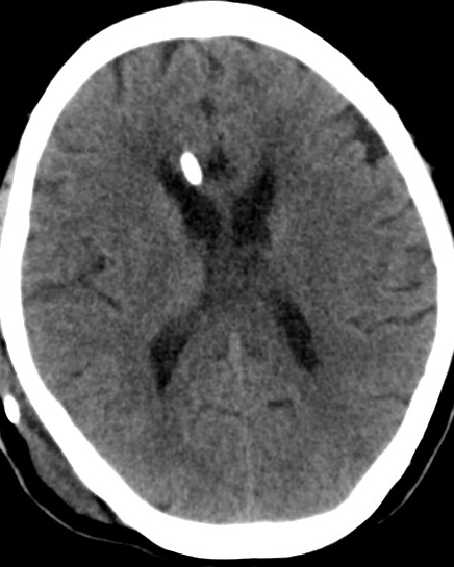

2013-8-2 CT

腰穿脑压240